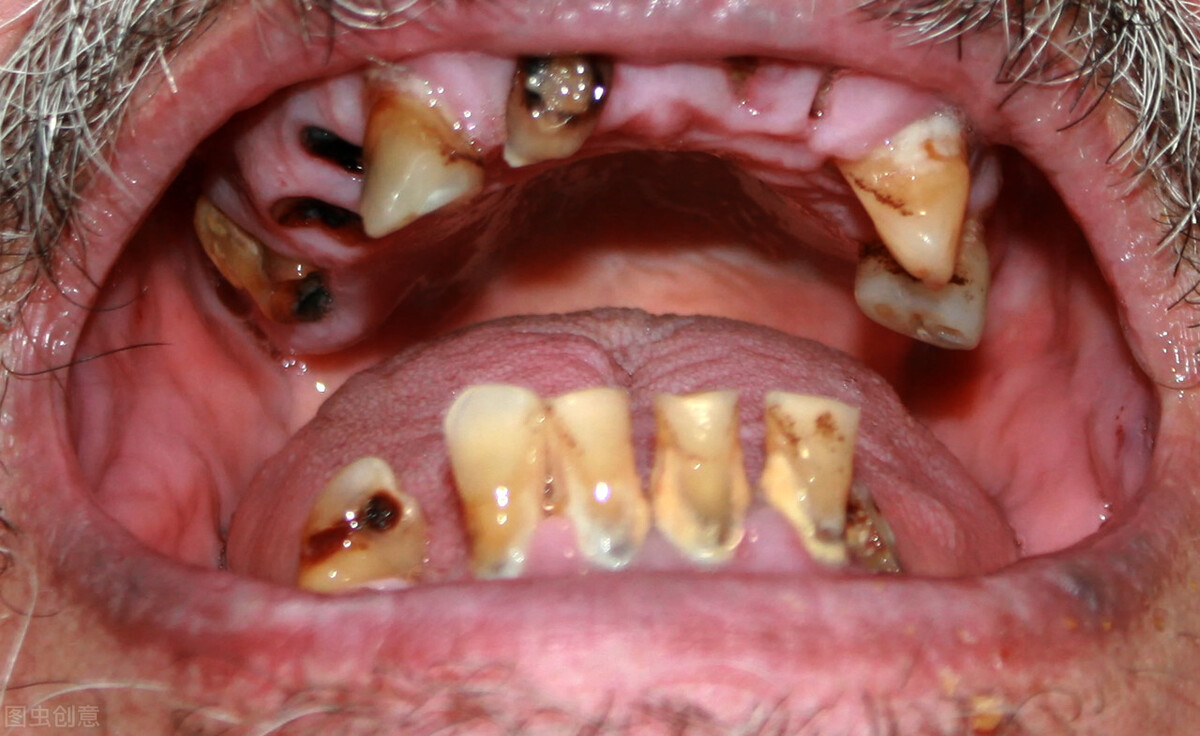

牙周炎不及时进行控制治疗,到了后期,牙槽骨吸收,牙周萎缩,牙根暴露,最终牙齿坏死,松动掉落。

一般患有牙周炎的患者,不进行控制治疗,牙周炎形成的脓包、牙周袋等会存在一股恶心的臭味,即便刷牙,也会出现口臭的症状。